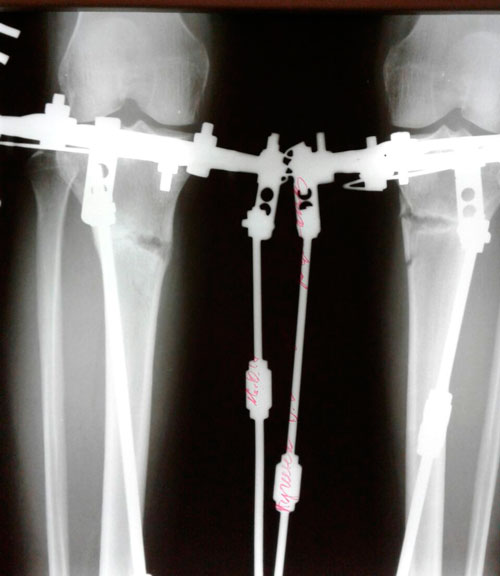

Дата операции - 11.07.2017г.

Дата снятия аппаратов 16.10.2017г.

Срок лечения 95 дней.

рентген и фото ножек, через 2 месяца с момента снятия аппаратов.

Сращение отличное, разрешено обувать каблучки, привыкайте к красивому!

Физические нагрузки разрешены (спорт) постепенно, по нарастающей.